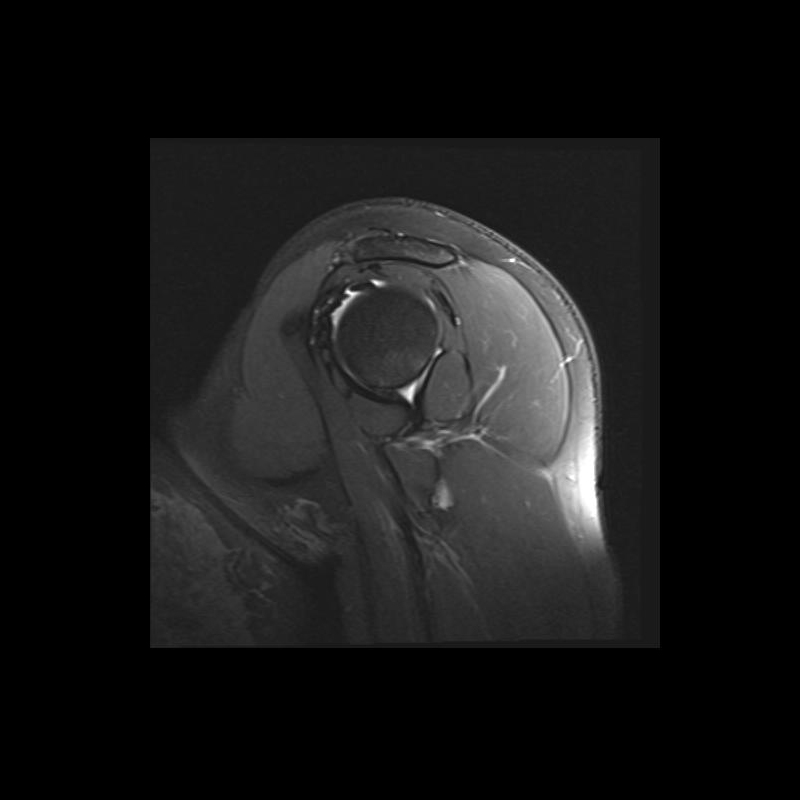

Shoulder MRI Anatomy